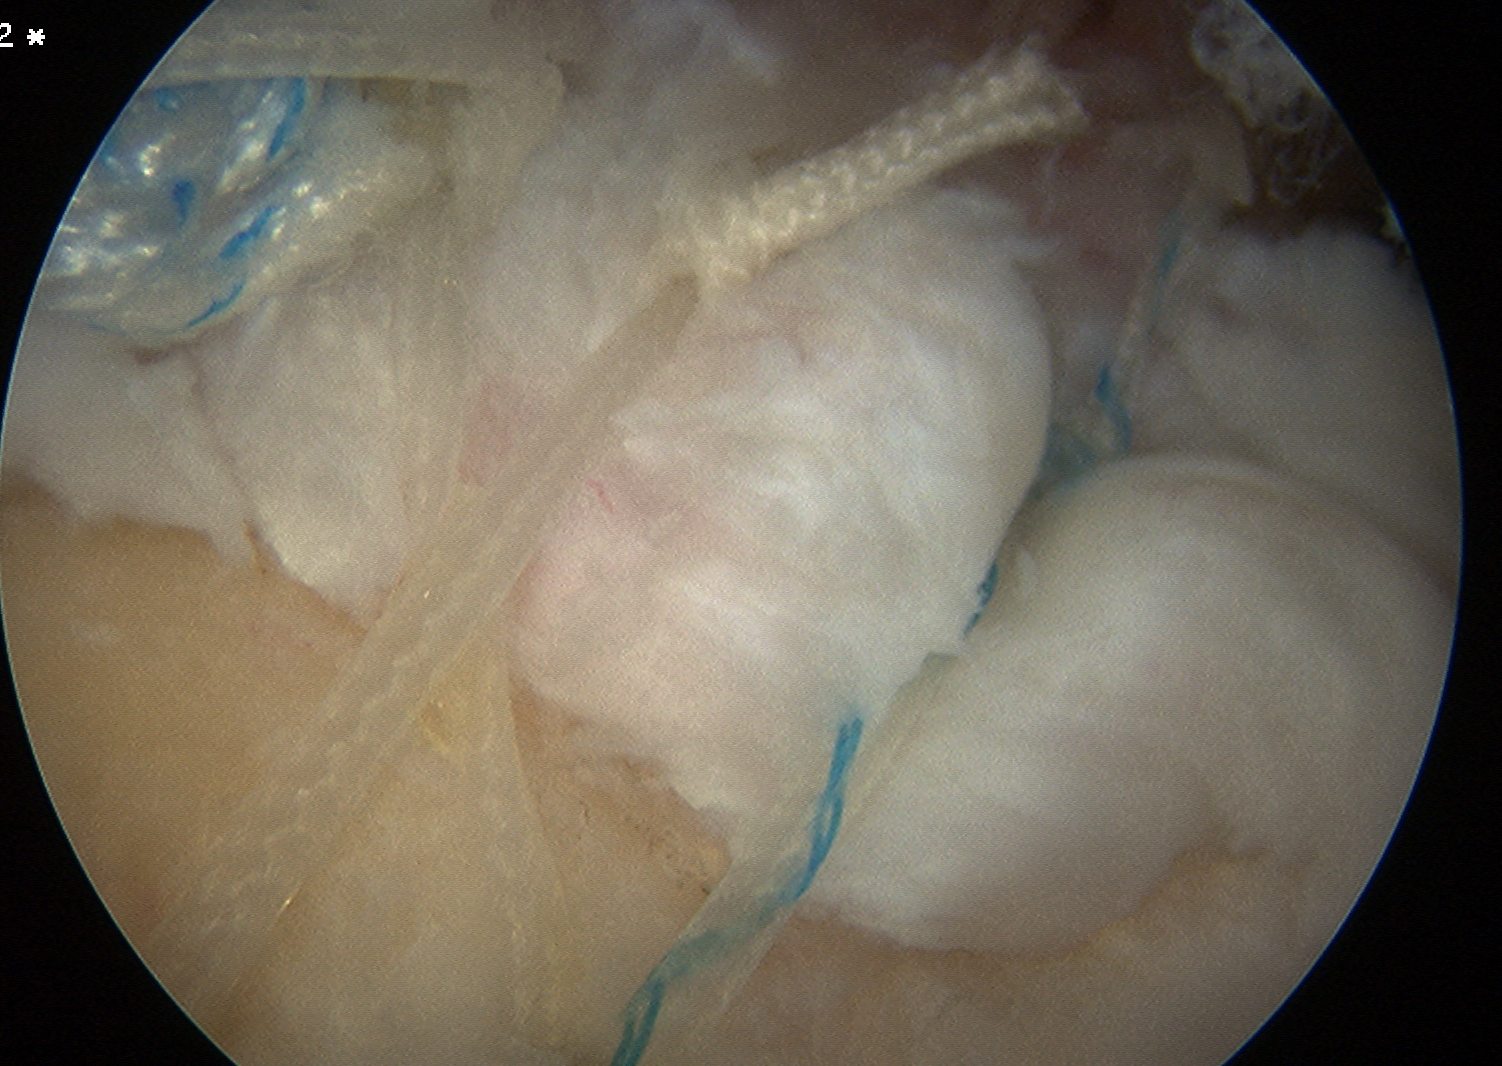

Tie sutures

- posterior to anterior / anterior to posterior

Double row

- either pass second lateral row of anchors or

- use foot print anchors, retrieve previous sutures

- can make suture bridge configuration

- check repair via lateral portal